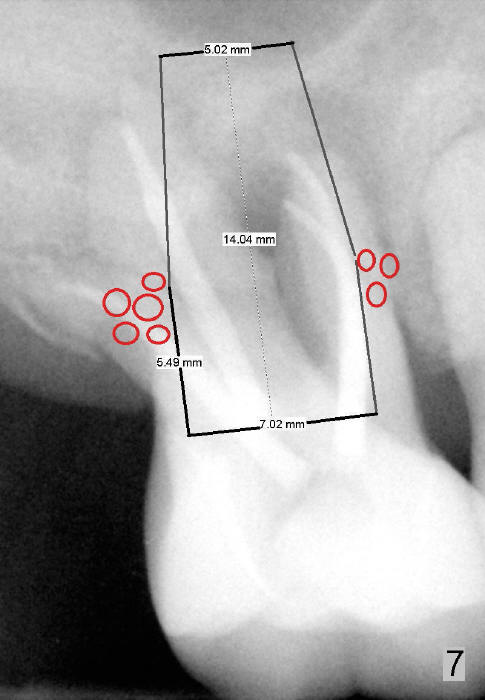

If primary stability is questionable with the bone-level implants mentioned above, a 7x14 mm gingiva-level implant will be the next alternative (Fig.7). If primary stability is still insufficient, a 7x17 mm (with sinus lift) or 8x14 or 17 mm will be placed (Fig.8). The larger the implant, the less bone graft is used (compare Fig.7,8).